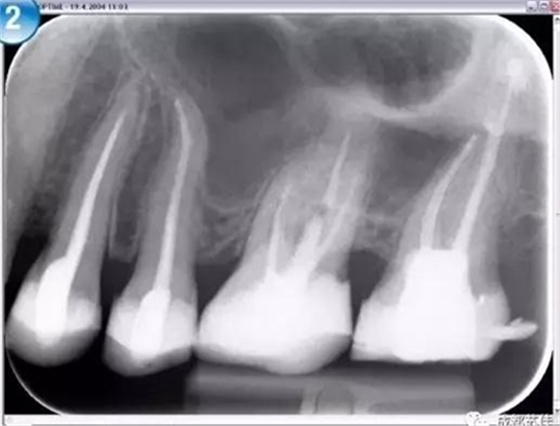

(2)超高空間分辨率及密度分辨率影像板完美的保證了成像質(zhì)量

Compass 2 使用最高敏感性和最智能的IP板讀取技術(shù)來獲取最高質(zhì)量的影像此外,Compass 2 允許減少曝光時間,從而減少欠曝和過曝。

空間分辨率最高可達16.7lp/mm,16位(65,636)的灰度,能夠可靠的分辨出D1級別的齲損及細小至ISO 06 級別的根管器械。

灰度值可自動調(diào)整,無需反復(fù)更改曝光設(shè)置也可獲得持續(xù)性的影像結(jié)果,影像讀取后只需微調(diào)即可獲得良好的影像減少過曝引起的偶然性。